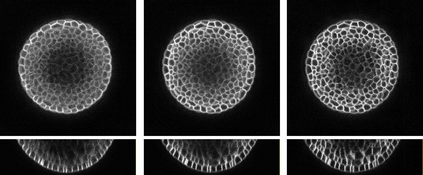

Automated image processing approaches are indispensable for many biomedical experiments and help to cope with the increasing amount of microscopy image data in a fast and reproducible way. Especially state-of-the-art deep learning-based approaches most often require large amounts of annotated training data to produce accurate and generalist outputs, but they are often compromised by the general lack of those annotated data sets. In this work, we propose how conditional generative adversarial networks can be utilized to generate realistic image data for 3D fluorescence microscopy from annotation masks of 3D cellular structures. In combination with mask simulation approaches, we demonstrate the generation of fully-annotated 3D microscopy data sets that we make publicly available for training or benchmarking. An additional positional conditioning of the cellular structures enables the reconstruction of position-dependent intensity characteristics and allows to generate image data of different quality levels. A patch-wise working principle and a subsequent full-size reassemble strategy is used to generate image data of arbitrary size and different organisms. We present this as a proof-of-concept for the automated generation of fully-annotated training data sets requiring only a minimum of manual interaction to alleviate the need of manual annotations.